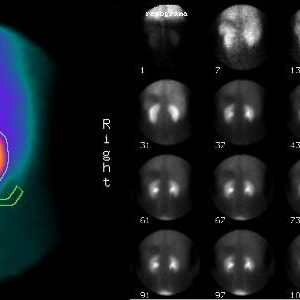

Una gammagrafía ósea implica inyectar una cantidad muy pequeña de material radiactivo (marcador) dentro de una vena. La sustancia viaja a través de la sangre hasta los huesos y órganos. A medida que esta va desapareciendo, emite un poco de radiación. Esta es detectada por una cámara que lentamente escanea el cuerpo.

Toma imágenes del marcador que hay en sus huesos. El técnico puede solicitarle que cambie de posición durante el procedimiento. Esto ayuda a obtener imágenes desde diferentes ángulos. Una gammagrafía ósea de todo el cuerpo tarda aproximadamente 1 hora en completarse.

La cámara gamma detecta las emisiones de energía de la radiosonda en su cuerpo y las convierte en una imágen. La cámara gamma de por sí no emite ninguna radiación. Tiene detectores de radiación denominados cabezas de cámara gamma.